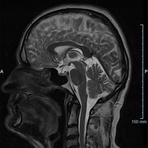

- Multiple Sklerose

- Diffusionswichtung

- Perfusionswichtung

- Suszeptibilitätswichtung

- MR-Spektroskopie

Diese Verfahren werden bei verschiedenen Fragestellungen in verschiedenen Körperregionen in die Messprotokolle sinnvoll eingefügt. Teilweise können dadurch Differenzierungenverschiedener krankhafter Prozesse verbessert werden.